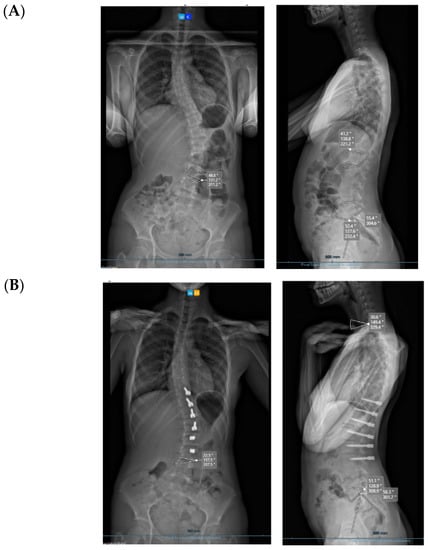

All cases have progressed well with improvement of the curvatures with growth (Table 1) both in the coronal and sagittal alignment. At the 6-month FU, there was a mean 67.5% (34.8°) improvement in the main Cobb angle, but at 1 y, the oldest case over-corrected, and this was clinically noted by the girl, who pointed out that her flank symmetry had recently inverted (from one side to the other) after being symmetrical for some time (Figure 6).

Figure 6.

Rib hump at 6 months (A) and 18 months (B). Follow up shows progressive improvement.

Concerning de-rotation, we can assess the apical vertebral rotation on the pre-operative radiograph as a Cobb grade +3 (Nash–Moe 50%) that improved to a Cobb grade +1 (Nash–Moe of 0%) in the last FU film (Figure 7) one year later.

Figure 7.

Apical improvement with progressive de-rotation of the vertebrae. (A) Pre-op. (B) FU at 1 year.

Figure 9.

Over-correction. (A) Pre-op (left) + 18-month FU (curvature apex corrects to the opposite side) (right). (B) Post tether release. (C) Immediate post-op erect radiograph.

3.1. Complications

The only case with a 15-month follow up progressed to coronal over-correction and had to be revised (under local anaesthetic) for tether release at four levels (Figure 9A,B). Since then, she has been doing well clinically and radiologically. This complication may have happened because correction obtained at the index procedure was too much, with a Cobb angle of 13.6° in the immediate post-operative erect radiograph (pre-op Cobb angle 56.7°) in a girl rated Sanders 3 (Figure 9C).